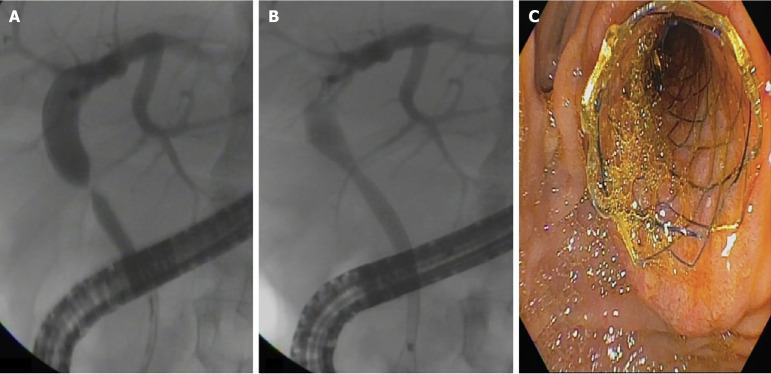

Background: Biliary anastomotic stricture (BAS) occurs in approximately 14%-20% of patients post-orthotopic liver transplantation (post-OLT). Endoscopic retrograde cholangiopancreatography (ERCP) using multiple plastic stents (MPSs) or fully covered self-expandable metal stents (cSEMSs) represent the standard treatment for BAS post-OLT. Recently, cSEMSs have emerged as the primary option for managing BAS post-OLT.

Methods: This retrospective cohort study was conducted in a single tertiary care center (Hospital Israelita Albert Einstein, São Paulo, Brazil). We reported the results of endoscopic therapy in patients with post-OLT BAS between 2012 and 2022. Patients were stratified into two groups according to therapy: (1) MPSs; and (2) cSEMSs. Primary endpoints were to compare stricture resolution and recurrence among the groups. The secondary endpoint was to identify predictive factors for stricture recurrence.

Results: A total of 104 patients were included. Overall stricture resolution was 101/104 (97.1%). Stricture resolution was achieved in 83/84 patients (99%) in the cSEMS group and 18/20 patients (90%) in the MPS group (P = 0.094). Failure occurred in 3/104 patients (2.8%). Stricture recurrence occurred in 9/104 patients (8.7%). Kaplan-Meier analysis showed there was no difference in recurrence-free time among the groups (P = 0.201). A multivariate analysis identified the number of ERCP procedures (hazard ratio = 1.4; 95% confidence interval: 1.194-1.619; P < 0.001] and complications (hazard ratio = 2.8; 95% confidence interval: 1.008-7.724; P = 0.048) as predictors of stricture recurrence.

Conclusion: cSEMSs and MPSs were effective and comparable regarding BAS post-OLT resolution and recurrence. The number of ERCP procedures and complications were predictors of stricture recurrence.